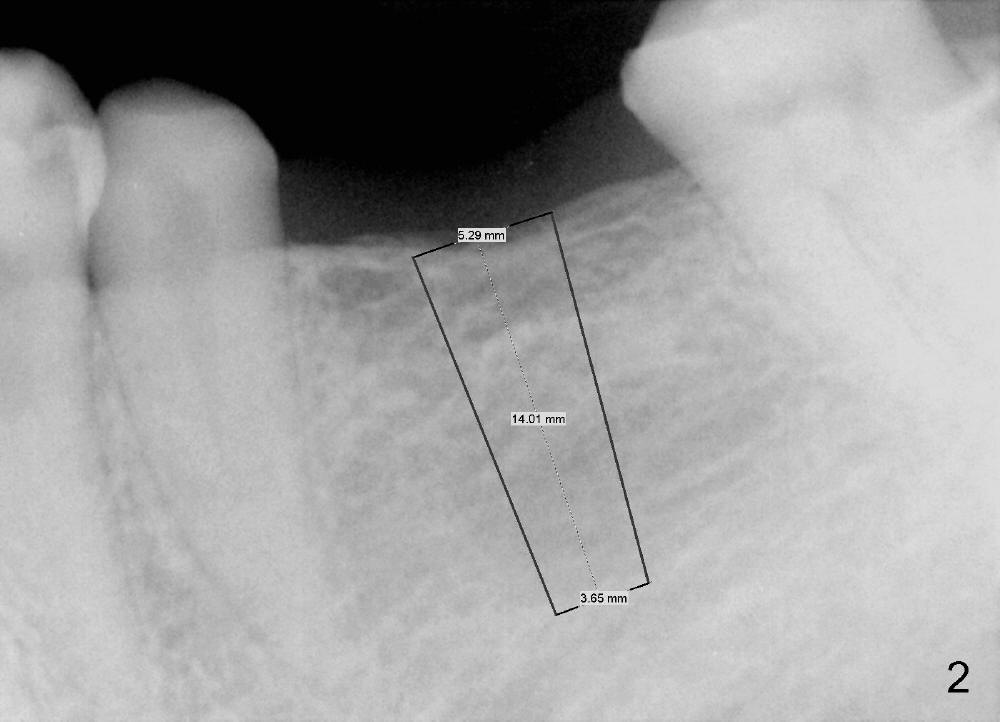

A 47-year-old man has lost a lower left fixed partial denture (FPD) for a while (Fig.1,2). There is limited space between the abutments (of the teeth #18 and 20) and the opposing dentition. The edentulous ridge is wide enough to use a 4 mm tissue punch. A 5.3x14 mm bone-level implant is to be placed (Fig.2). The base of the implant is at the level of the apices of the neighboring teeth. As compared to Fig.1 in term of the Inferior Alveolar Canal (yellow line), there should be enough safe margin. The first intraop PA is taken after 2 mm pilot drill for depth and trajectory check, Drill stops are to be used for safety. If primary stability is achieved, an abutment is placed and a provisional bridge will be fabricated to prevent further narrowing of the interocclusal clearance during 3-4 months of osteointegration. How is outcome?